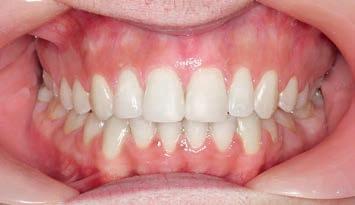

Figs. 9a–c: Situation after 1 month of correction with Sagittal First approach. – Figs. 10a–c: Situation after 2 months of correction. – Figs. 11a–c: Situation after 3 months of correction: Class I achieved. – Figs. 12a–c: Situation after 4 months of treatment (3 months of Motion sagittal treatment and 1 month in fixed appliances). .014 x .025 wire with power chain to close the spaces between the incisors. – Figs 13a–c: Situation after 7 months of treatment (3 months of Motion sagittal treatment and 4 month in fixed appliances). .019 x .025 archwire was engaged with power chain to retract the anterior segment and bring it into the final desired position. – Figs 14a–c: Final situation achieved after 11 months of treatment (3 months of Motion sagittal treatment and 8 months of Carriere SLX fixed appliance therapy).